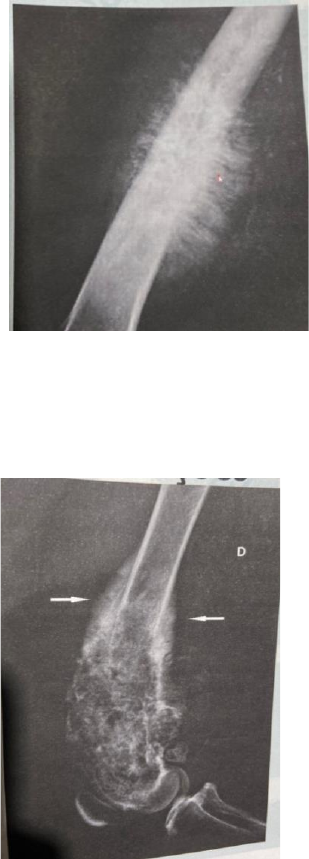

<p>Reações periosteais são as:</p><p>Reação em raios de sol: Que são caracterizadas por espiculas ósseas que irradiam de uma</p><p>lesão osteolidica (manchas de danos ossos) ou ostoprodutiva agressiva, acontece</p><p>principalmente em tumores ósseos malignos</p><p>Triângulo de codman: Reação caracterizada pela elevação do periósteo, resultando em</p><p>neoformação óssea subperiosteal em forma triangular. Ocorre frequentemente em nas</p><p>neoplasias primária malignas, embora também possa ser visualizado em osteomielites</p><p>Reação espiculada ou em paliça: Caracteriza-se como uma neo- formação óssea que se irradia</p><p>per- pendicularmente ao córtex do osso longo. É observada frequente- mente na osteopatia</p><p>hipertrófica e ocasionalmente, na osteomielite.</p><p>Lamelar ou em casca de cebola: é caracterizada pela deposição de múltiplas camadas ósseas</p><p>recém-formadas, paralelas à cortical do osso, que podem assumir o aspecto de “cascas de</p><p>cebola,, resultante de repetidos estímulos, processos irritativos e traumas</p><p>Regular e sólida: é típica de traumas focais em que há hematoma subperiosteal e parte do</p><p>periósteo se distancia do córtex.. É uma reação característica de processos crônicos, podendo</p><p>representar a resolução de outros tipos de periostites</p>